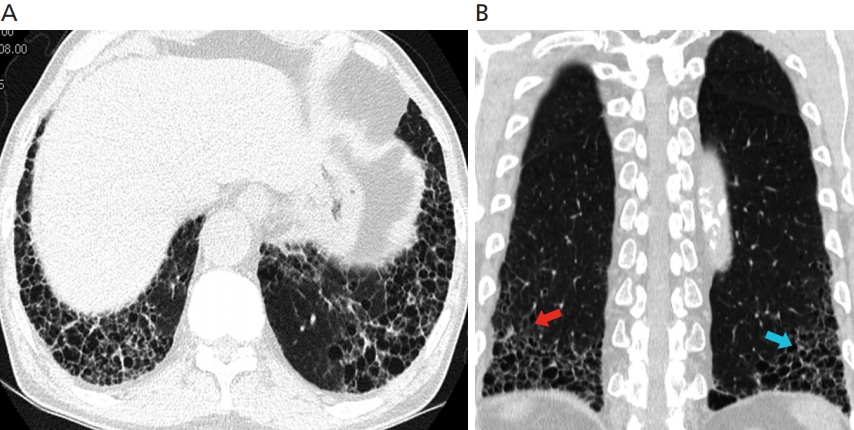

- 진단: 흉부 CT, 폐 기능 검사, 조직 생검 등을 활용

- 고해상도 흉부 CT와 폐조직 검사, 다양한 감별진단(자가면역질환, 약물, 환경성 노출 가능성 배제) 과정이 필요합니다.